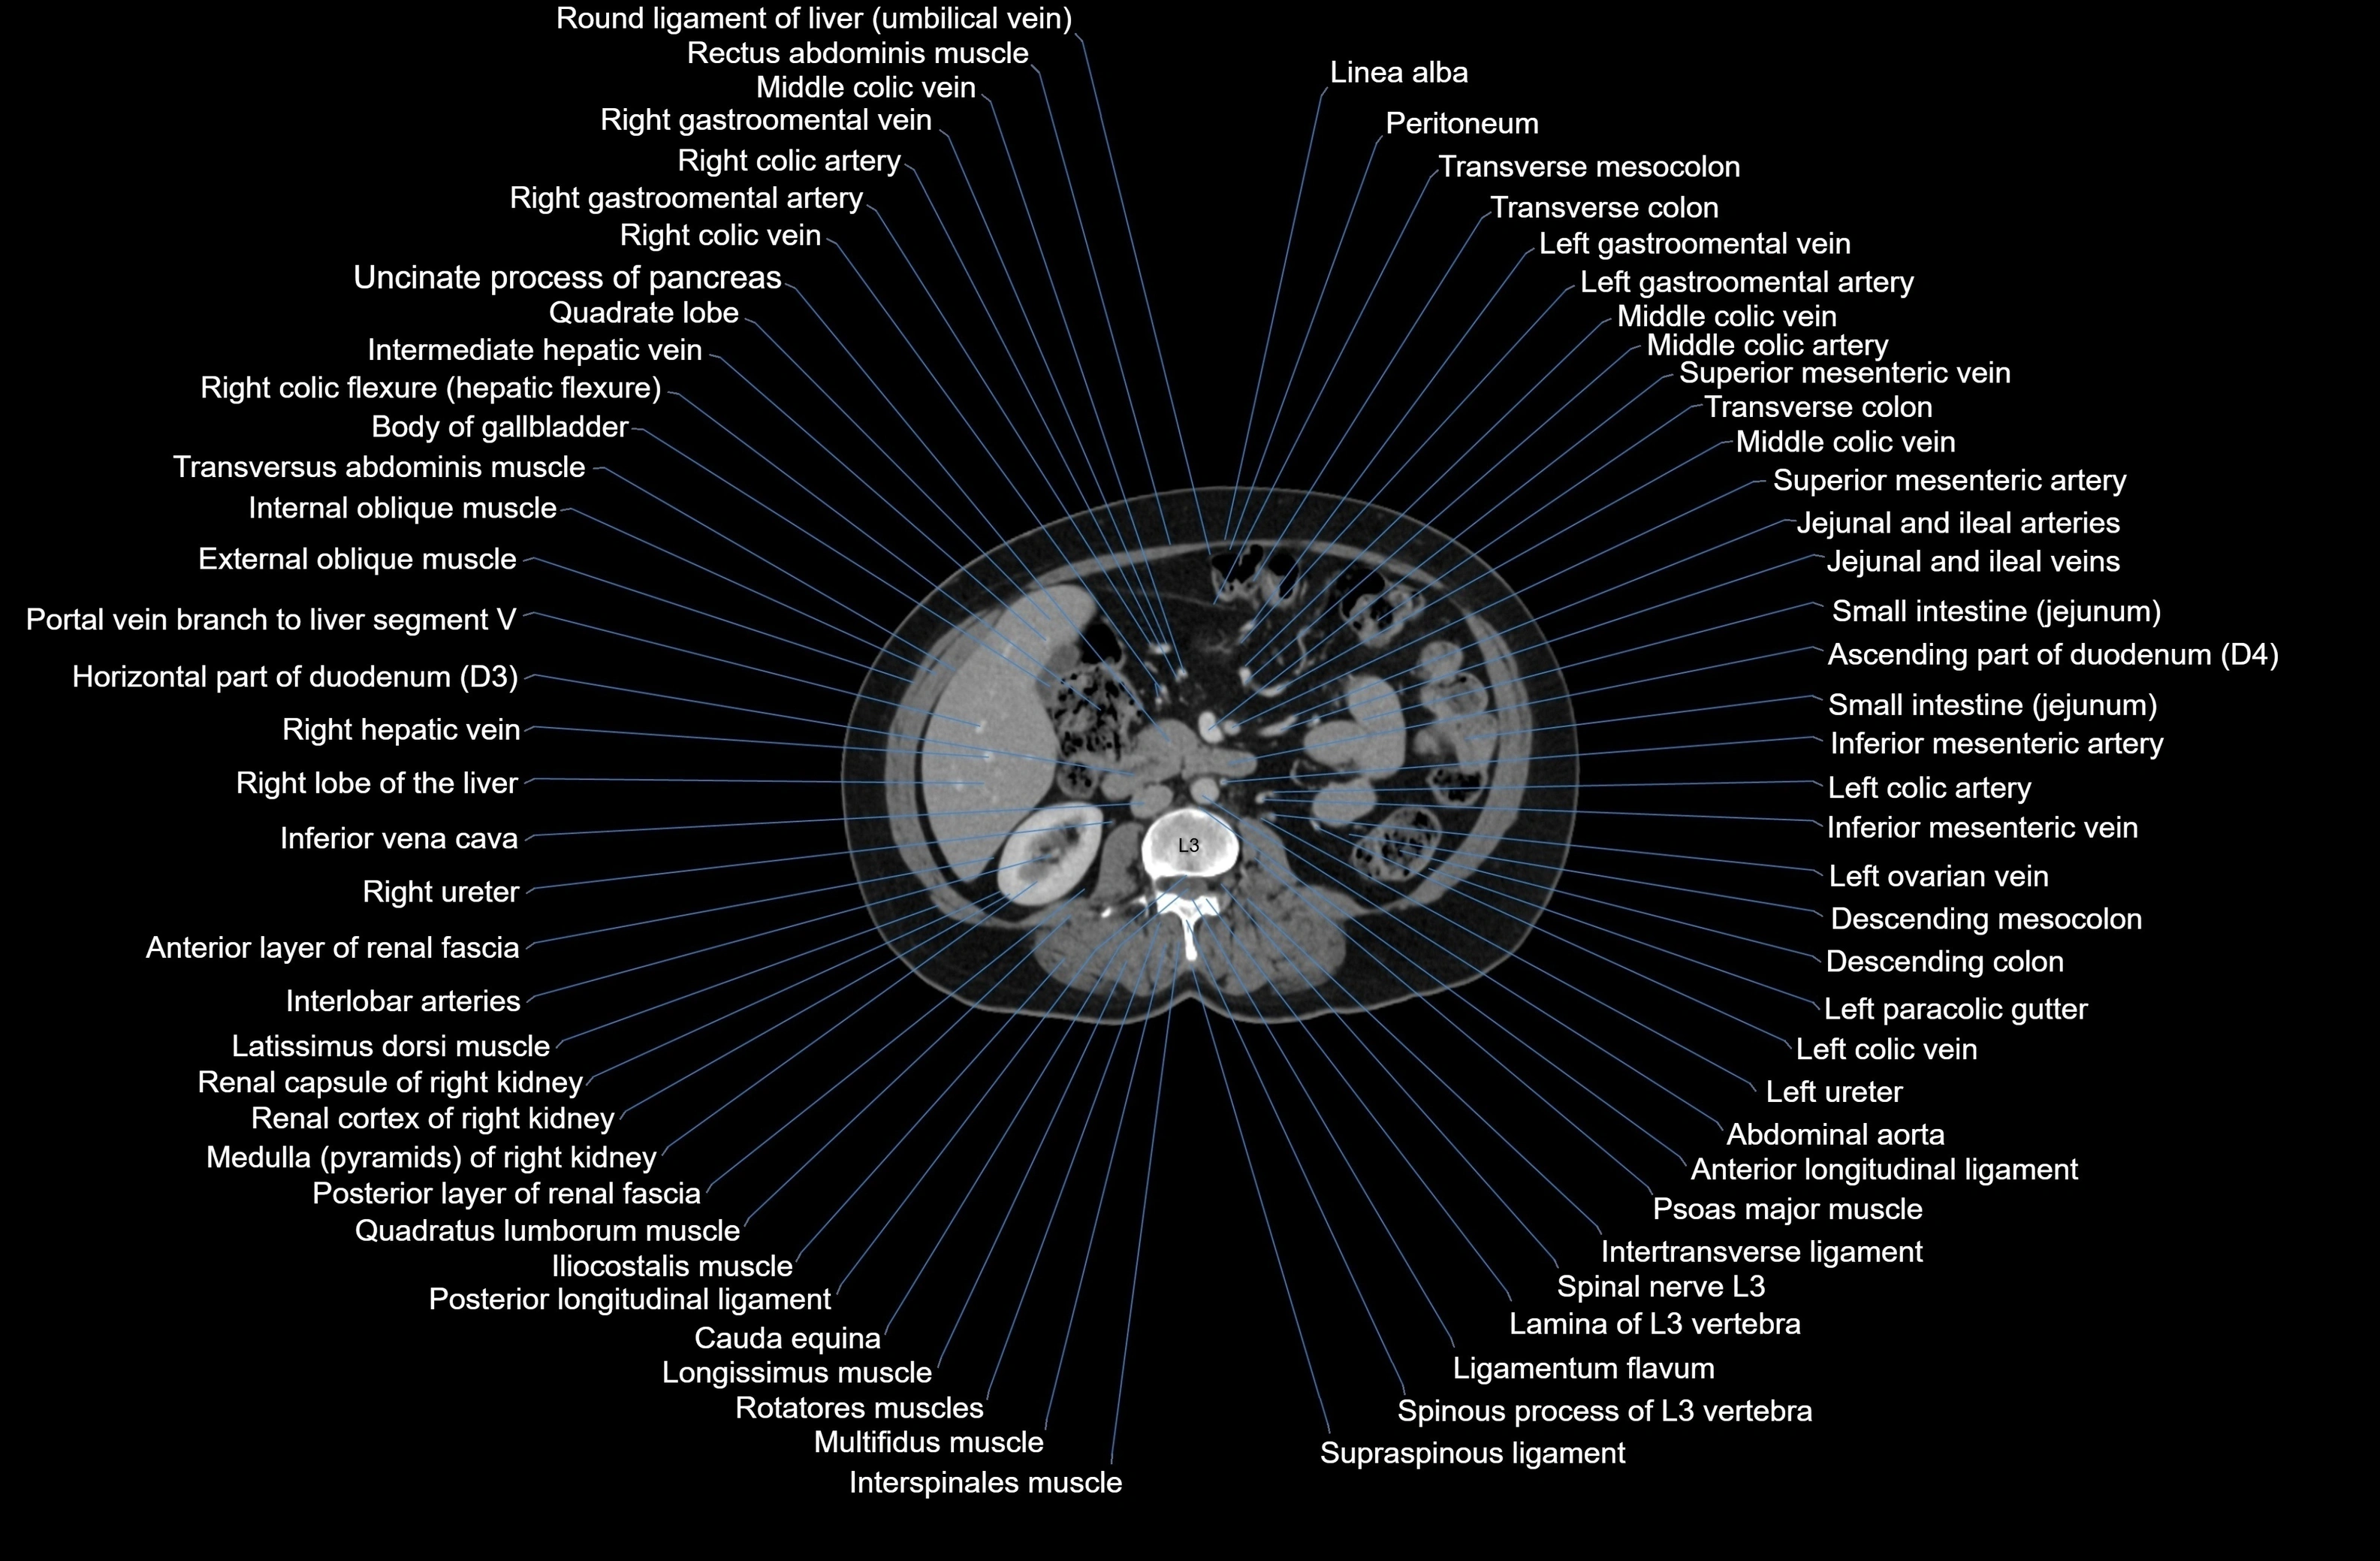

CT images